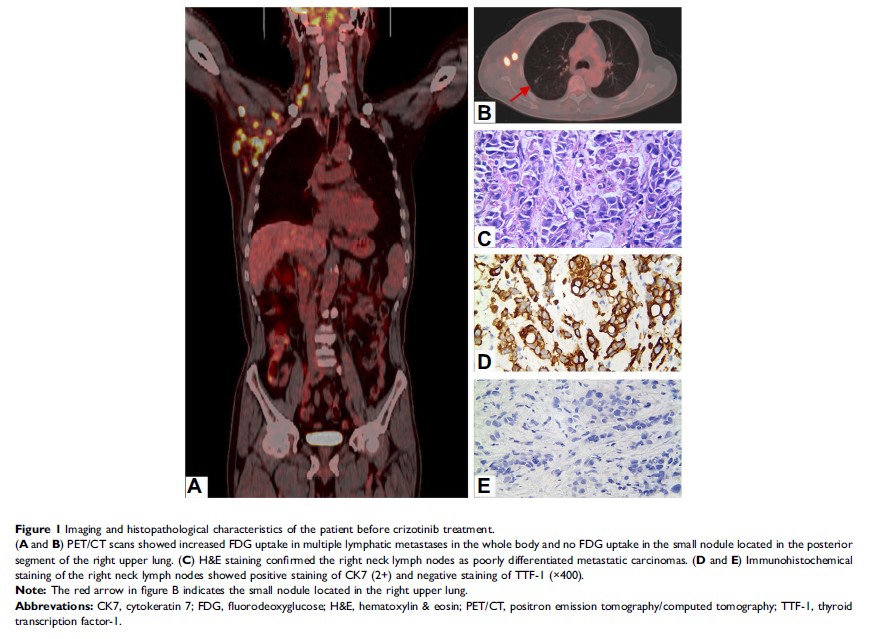

克唑替尼治疗 MET 扩增和 NTRK 1 共突变的原发灶不明转移性腺癌并获得完全缓解一例